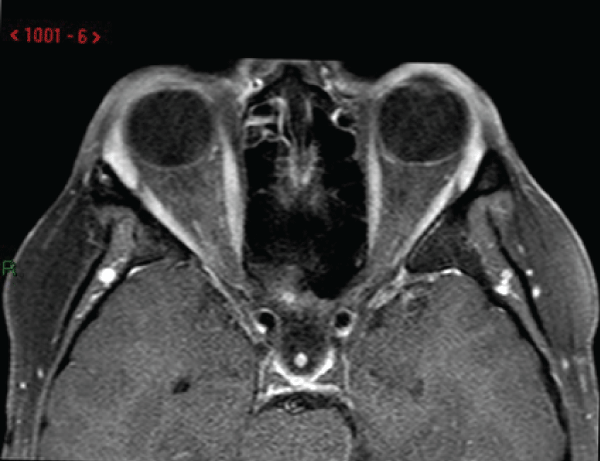

A recent case report demonstrates the novel use of these two agents in the treatment of orbital IRD in a 32 year-old woman who presented with an 18-month history of diplopia, proptosis and headaches (Figure 1A, Supplemental Figure 1A) [44]. An MRI scan showed an ill-defined, intra-conal lesion causing 5mm of proptosis and displacement of the optic nerve supero-medially (Figure 2).

Figure 2: Axial T1 post-contrast MRI sequence showing a large ill-defined

intra-orbital mass that occupied most of the intra-conal space extending from

the globe to the orbital apex displacing the optic nerve supero-medially and

5mm of proptosis. Reproduced with permission from BJOMFS [44].

View Figure 2